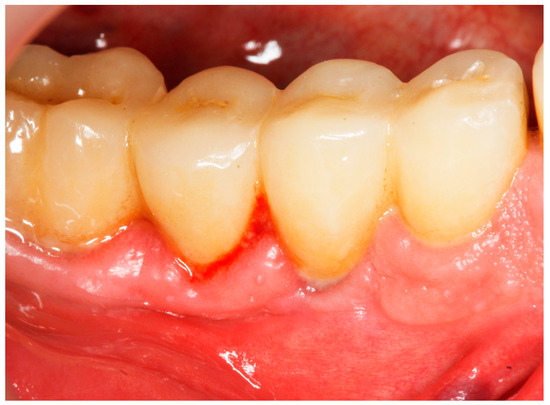

2.8. Treatment Procedures

2.9. Evaluation of Treatment Effect